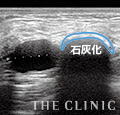

32歳・10年前に挿入

乳腺と大胸筋の間に4cmのしこりを確認。10年前に注入した脂肪が壊死している状態です。エコー検査をしたとき、超音波を反射して黒くなっていることから、しこりの周囲がカルシウムが沈着して石灰化していることが分かりました。このような場合は切開して摘出する治療法がベストです。